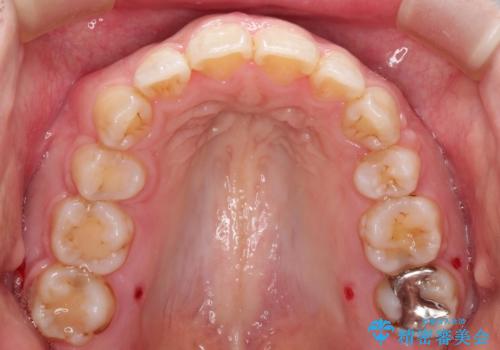

- ガタガタと出っ歯を主訴に来院されました。

上下左右の歯を1本ずつ、合計4本抜歯してワイヤーにて矯正治療をすることとなりました。

前から4番目の歯を抜歯することが多いのですが、右上の前から5番目の歯が神経の治療済みであり、こちらの歯を抜歯する計画としました。

通常より治療期間を要しましたが、健康な歯を残すことができました。